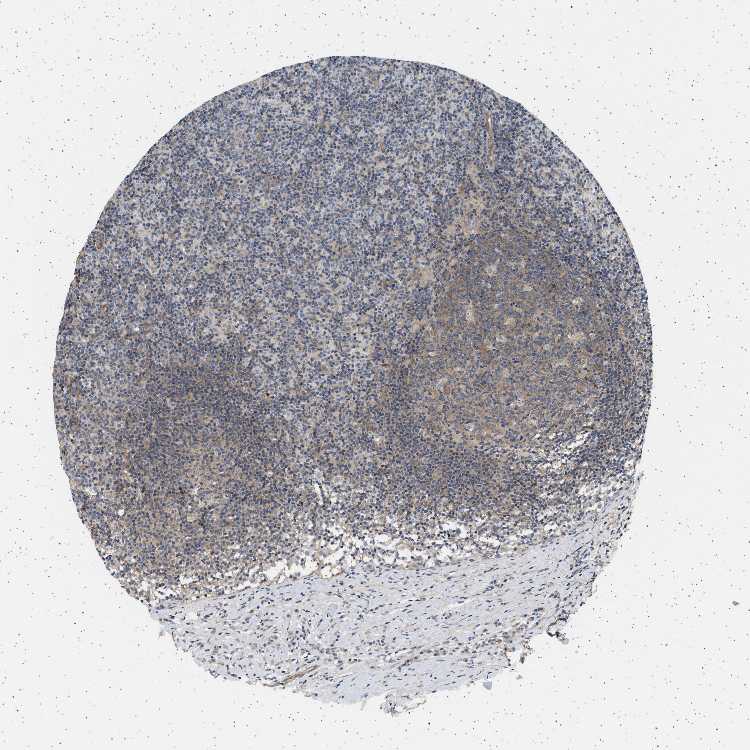

LYMPH NODE - Antibody stainingi

Antibody staining in the annotated cell types in the current human tissue is reported as not detected, low, medium, or high, based on conventional immunohistochemistry profiling in selected tissues. This score is based on the combination of the staining intensity and fraction of stained cells.

Each image is clickable and will lead to virtual microscopy that enables deeper exploration of all samples and also displays staining intensity scores, fraction scores and subcellular localization as well as patient and tissue information for each sample.

Antibody HPA018096

Germinal center cells Medium

Non-germinal center cells Medium